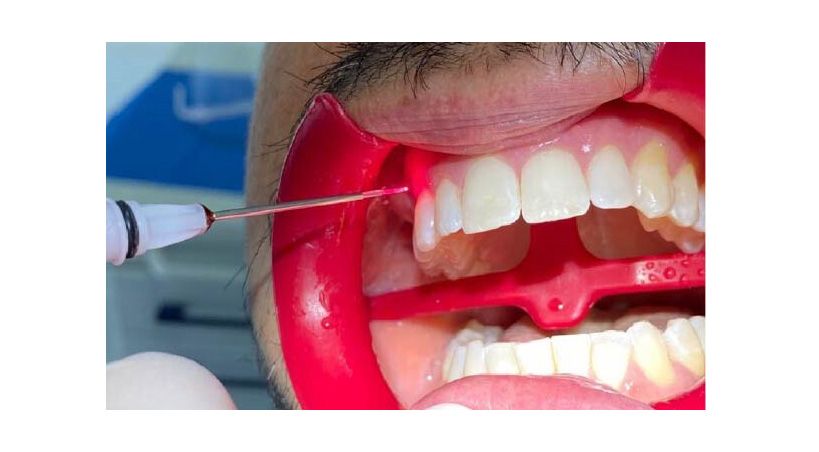

Odontología General

Dispositivos dentales y resistencia antimicrobiana

Desafíos, innovaciones y cumplimiento normativo